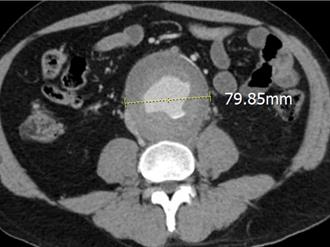

台中70多歲江姓老翁日前突發劇烈腰痛腹痛,急送台中慈濟醫院緊急檢查發現腹主動脈瘤破裂,命懸一線,院方心臟血管外科醫師鄭伊佐帶領團隊緊急施行微創手術,搭配去年9月納入健保給付的血管內錨釘技術,成功穩定病情,不僅救命,還為病人省下近40萬元醫療費用。

有腎結石病史的55歲高先生日前出現腰痛、背痛,他以為是結石復發,經影像檢查,發現是腹部長出8公分大的腹主動脈瘤。台北慈濟醫院心臟血管外科楊凱文醫師以微創手術替病人置放難度較高且臨床較少使用的T分枝主動脈支架,先避免主動脈瘤立即破裂的風險,再於術後14天執行冠狀動脈繞道手術,同時解除主動脈瘤破裂和心肌梗塞的危機。